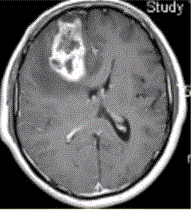

问题 患者女,67岁,头痛伴呕吐1周。既往体健。MR表现如下图。 胶质瘤术后放疗后复发与放射性坏死的鉴别手段是

选项 A.T2* B.PWI C.DWI D.Gd-MRI E.FLAIR

答案 B